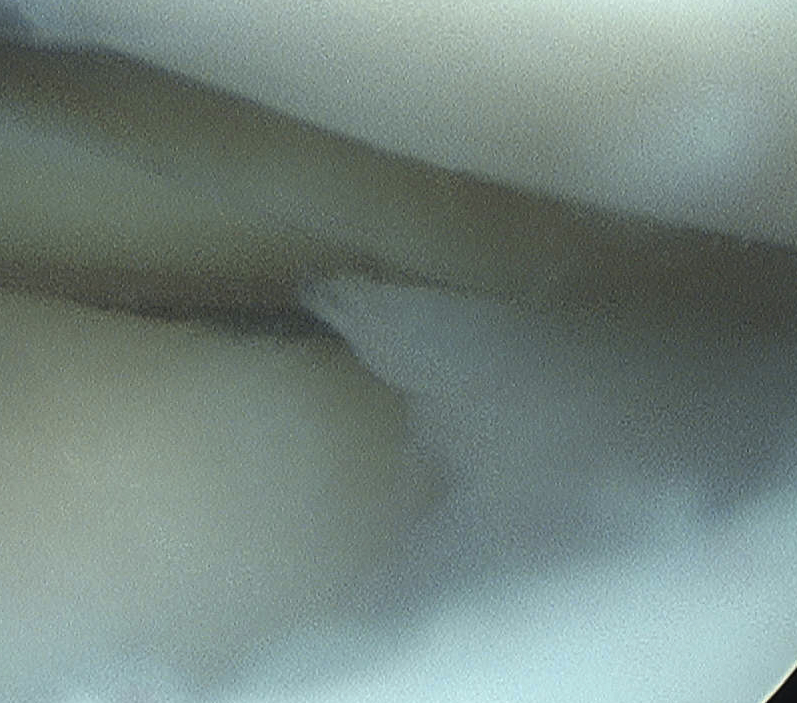

Arthroscopy

Mainstay of diagnosis and treatment

C. Bucket handle

- displaces into intercondylar notch

- may be central or peripheral

- cause of locked knee

- can damage chondral surface over time

Signs of bucket handle tear meniscus

1. Double PCL sign

- medial Meniscus

2. Absent bow tie sign

- should see bow tie image on 2 consecutive sagittal slices of 5 mm

3. Fragment in notch sign

4. Anterior flipped meniscal sign

- torn fragment flips over the anterior horn of the affected meniscus

5. Truncated meniscus